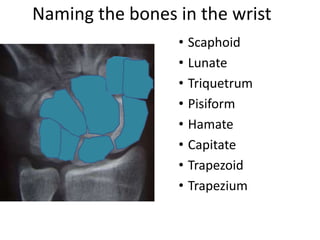

- Naming the bones, joints, tendons, nerves and skin landmarks of the hand and wrist.